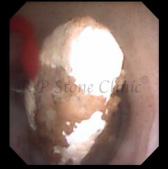

The Images Below are of Kidney Stones taken as snapshots from the video recording of RIRS Surgery done at our hospital with Digital Flexible Ureteroscopes, Flex XC and Flex XC S.